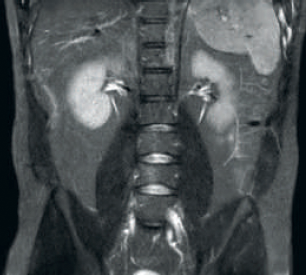

Result: Improved SNR and image resolution

Result: Noisy images using identical scan parameters